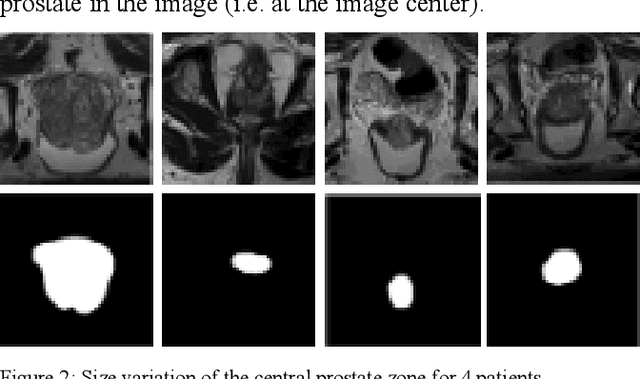

Abstract:Prostate segmentation from magnetic resonance imaging (MRI) is a challenging task. In recent years, several network architectures have been proposed to automate this process and alleviate the burden of manual annotation. Although the performance of these models has achieved promising results, there is still room for improvement before these models can be used safely and effectively in clinical practice. One of the major challenges in prostate MR image segmentation is the presence of class imbalance in the image labels where the background pixels dominate over the prostate. In the present work we propose a DL-based pipeline for cropping the region around the prostate from MRI images to produce a more balanced distribution of the foreground pixels (prostate) and the background pixels and improve segmentation accuracy. The effect of DL-cropping for improving the segmentation performance compared to standard center-cropping is assessed using five popular DL networks for prostate segmentation, namely U-net, U-net+, Res Unet++, Bridge U-net and Dense U-net. The proposed smart-cropping outperformed the standard center cropping in terms of segmentation accuracy for all the evaluated prostate segmentation networks. In terms of Dice score, the highest improvement was achieved for the U-net+ and ResU-net++ architectures corresponding to 8.9% and 8%, respectively.